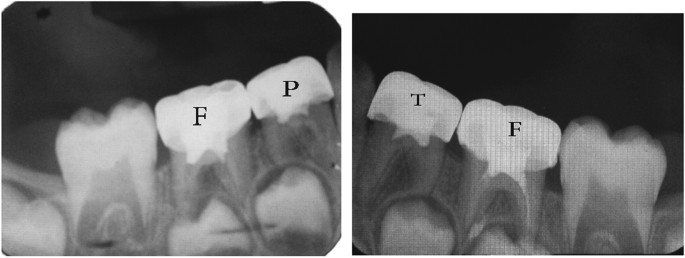

The teeth in the formocresol group had a clinical success rate of 100% at 1 month, 94.4% at 6 months and 88.2% at 12 months (Figures 2,3,4,5,6,7,8). The teeth in the propolis group had a clinical success rate of 94.7% at 1 month, and 88.2% at 6 and 12 months. The thymus vulgaris group had a clinical success rate of 94.4% at 1 month, and 94.1% at 6 months and 12 months follow-up. Statistical analysis of the data, using Friedman’s test, revealed no statistically significant differences between the three groups at all follow-up appointments (Table 1).

The teeth in the formocresol group had a radiographic success rate of 95.0% at 1 month, 81.2 at 6 months and 73.3% at 12 months. The teeth in the propolis group had a radiographic success rate of 94.7% at 1 month, 81.2% at 6 months and 73.3% at 12 months. The thymus vulgaris group had a radiographic success rate of 94.4% at 1 month, and 87.5% at 6 and 12 months. Statistical analysis of the data, using Friedman’s test, revealed no statistically significant differences between the three groups at all follow-up appointments (Table 2).